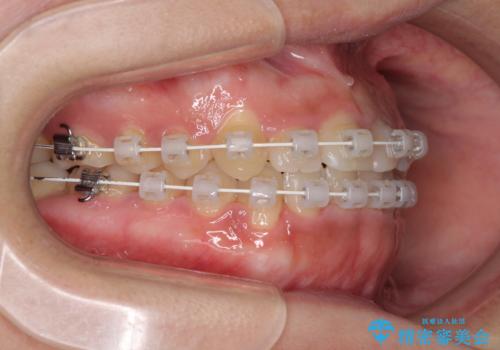

前歯の反対咬合 非抜歯のワイヤー矯正

- 審美装置

マウスピース矯正の自己管理が面倒くさいことと、治療を早く終わらせたいとのことで、目立ちにくいワイヤー矯正にて歯列を整えることとしました。

1年半はかかると思っていた治療期間ですが、反対咬合となっている前歯が思いの外早く動き、僅か9ヶ月で終了させることができました。